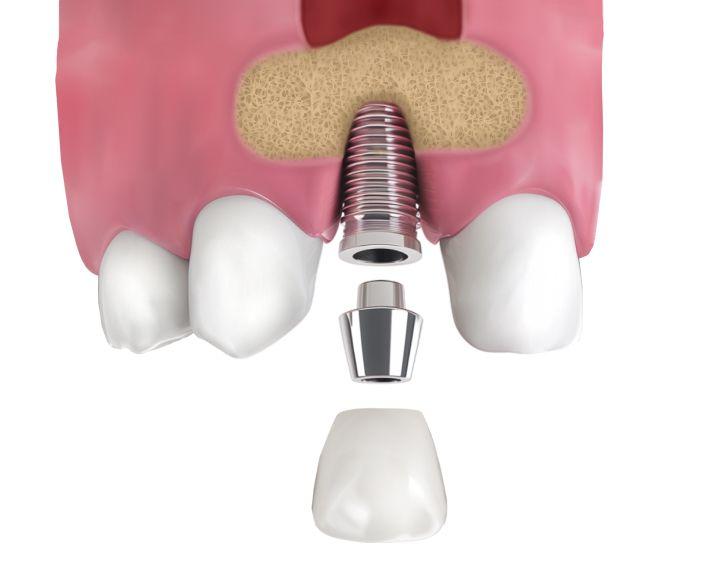

После формирования достаточного объёма кости выполняется имплантация. В ряде случаев возможно одномоментное проведение синус-лифтинга и установки импланта. Мы сопровождаем пациента до полного заживления и проводим осмотры, чтобы убедиться в правильном восстановлении тканей и готовности к имплантации.

• Далее в подготовленную область помещается костный материал. При достаточном объёме — сразу устанавливается имплант, при недостаточном — имплантация планируется после приживления.

• Согласовывается срок установки импланта, если она не была выполнена сразу.

• После формирования достаточного объёма костной ткани проводится имплантация и начинается этап протезирования.